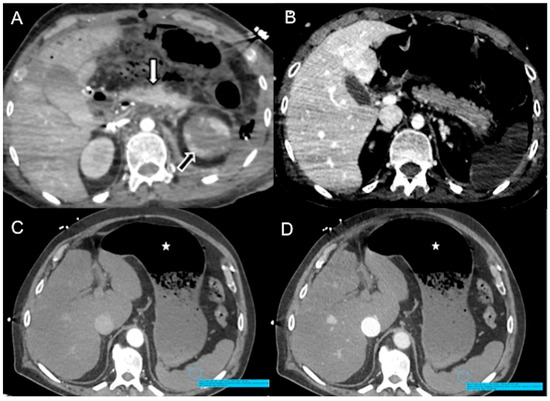

- In irreversible end-organ dysfunction, injected IV CM circulation is supported only by the pressure applied by the automated power injector and the density of contrast material. Circulatory arrest leads to dense contrast pooling and layering in the SVC, IVC (inferior vena cava), and right heart chambers with non-opacified left heart chambers or arterial vessels (Figure 1) [43,45,49,50,51,52]. This may be called the “non-beating heart” pattern. Cardio-pulmonary aggressive resuscitation must immediately be initiated within the framework of a predetermined emergency plan.

Figure 1. Non-beating heart in a 72-year-old man with sudden-onset severe dyspnea/shock and asystole during thoraco-abdominal CT. (A) CECT axial image shows dense contrast in the round superior vena cava, and reflux in the azygous arch; (B) contrast pooling and layering in the right atrium and IVC with retrograde opacification of coronary sinus (arrow). (C) CM fills the round inferior vena cava with hypostatic reflux into the hepatic veins, hemiazygos vein, partially splenic vein, and (D) right renal vein. Note no mixing of blood with CM and no opacification of the pulmonary arteries, aorta, and left cardiac chambers, suggestive of a non-beating heart. Prompt initiation of cardio-pulmonary resuscitation to restore circulation was useless. Autopsy: ruptured myocardial infarction.